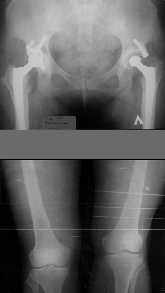

1. Иллюстрации - во вложении.

Два бедра после эндопротезирования.

Авторы операции долго думали почему больная хромает.

Сдклали снимок - одна нога короче почти на 3 см.

2. Другой пример - дефект после инфицирования коленного эндопротеза.

Предполагалось, что величина дефекта 11-12 см. Так получается, если

сделать снимок только области коленных суставов. Определить

укорочение сложно, так как нога просто болтатется.

Сделали снимок "от и до" - величина дефекта 17 см.

Правда эта иллюстарция сделана на цифровом рентгеновском аппарате.

Больной стоит, а трубка передвигается сверху вних, последовательно

выполняя рентгенограммы. В данном случае - 4 штуки.